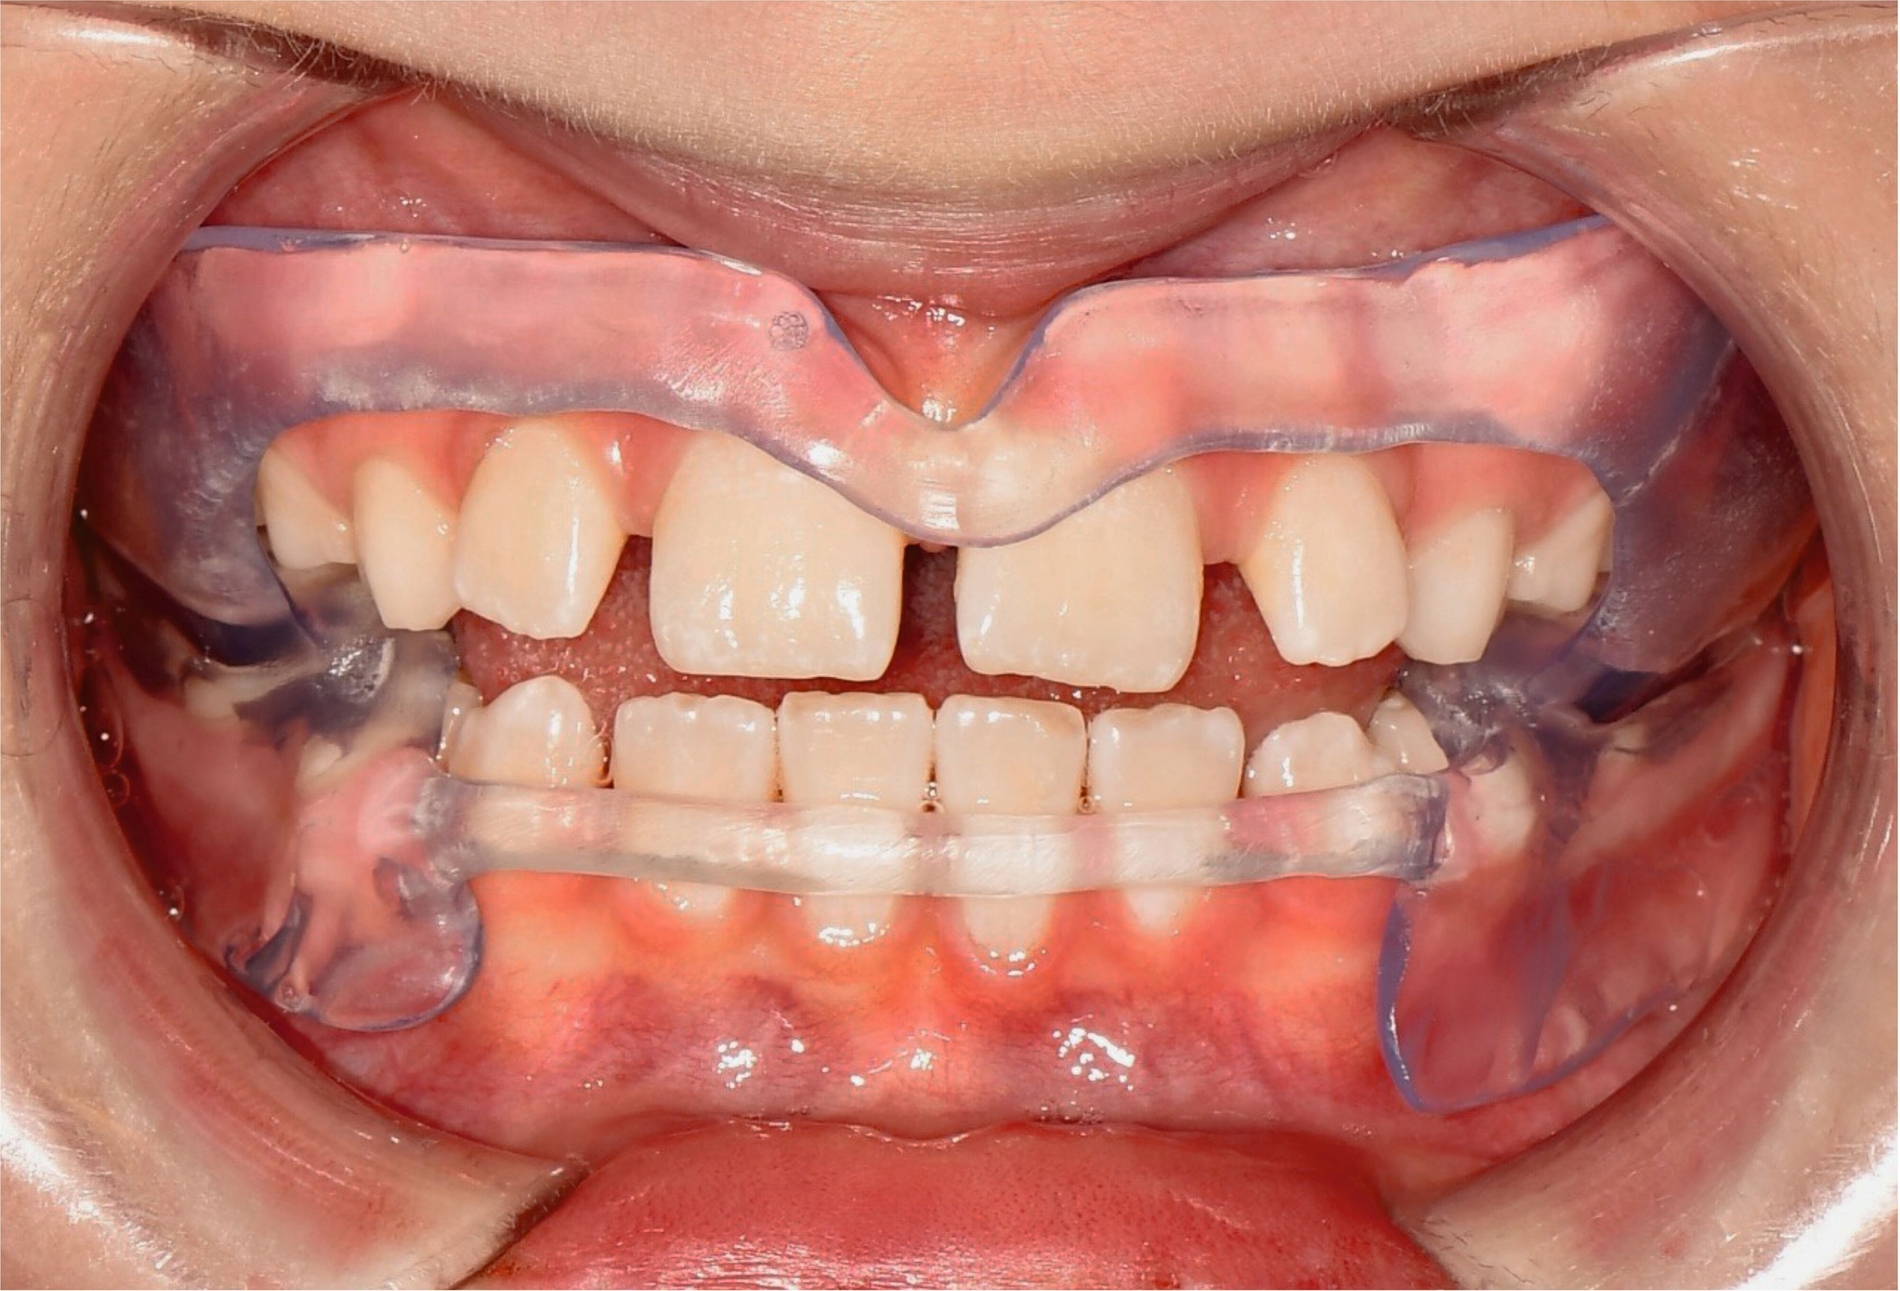

Als hochinnovatives Feld hat sich auch die Herstellung herausnehmbarer Apparaturen im 3-D-Druck entwickelt (Abbildung 4), beschränkt sich jedoch noch auf einzelne Forschungsansätze [Al Mortadi et al., 2012; van der Meer et al., 2016; Graf et al., 2022; Keller et al., 2022]. Intensiv an neuen Konzepten in der Herstellung 3-D-gedruckter herausnehmbarer Apparaturen wird am Universitätsklinikum Heidelberg geforscht. Da herausnehmbare kieferorthopädische Apparaturen im Regelfall bei jungen Patienten eingesetzt werden, kommt dem Vorteil einer unbegrenzten Replikation und einer kostengünstigen und schnelleren Herstellung ein besonderer Stellenwert zu.

Im Unterschied zu konventionellen Apparaturen bestehen die 3-D-gedruckten Apparaturen vollkommen aus Kunststoff. Eine Einarbeitung metallischer Elemente nach dem 3-D-Druck ist möglich [Al Mortadi et al., 2012; Al Mortadi et al., 2024], erfordert jedoch zusätzlichen Zeitaufwand. Zur Herstellung herausnehmbarer Apparaturen eignen sich konventionelle praxisinterne 3-D-Stereolithografie-Drucker, die in vielen Fällen bereits im regulären Praxisalltag zum Modelldruck verwendet werden. Die verwendeten Kunststoffe sollten dabei eine Klasse-IIa-Zertifizierung aufweisen, so dass ein sicherer langfristiger intraoraler Einsatz der Apparatur gewährleistet ist. Weiter muss die Apparatur nach dem 3-D-Druck gemäß den Herstellerangaben nachprozessiert werden. Im Regelfall beinhaltet dieser Prozess ein Waschen in Isopropylalkohol (IPA) sowie eine Nachhärtung im Lichthärtegerät. Eigens durchgeführte Studien sowie die bisherige klinische Erfahrung bestätigen eine hohe mechanische Stabilität, eine hohe Passgenauigkeit sowie eine breite Akzeptanz der Patienten [Roser et al., 2021; Roser et al., 2023; Segnini et al., 2023]. Des Weiteren wecken die 3-D-gedruckten Apparaturen bei den meist jungen Patienten großes Interesse, was wiederum die Trage-Compliance unterstützt. Durch weitere Entwicklungen im 3-D-Druckbereich wird zukünftig auch ein Farbdruck möglich werden.